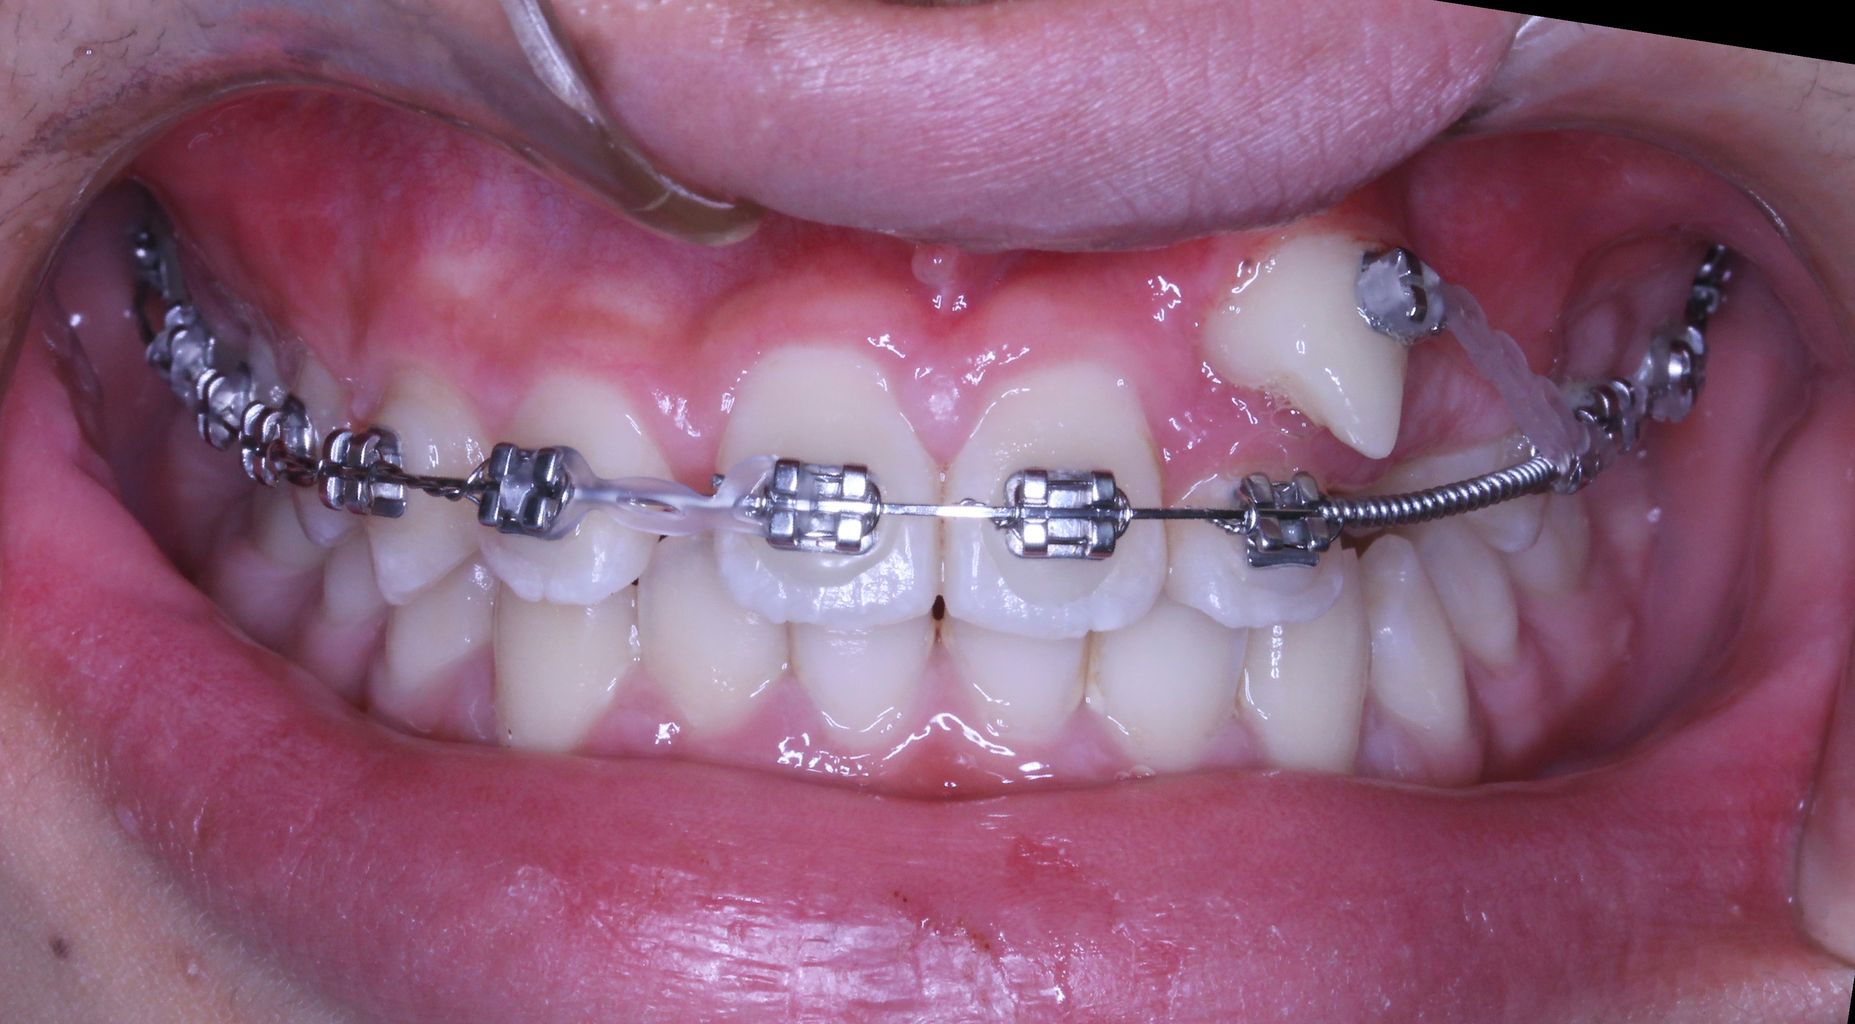

現在の状況はもう少し治療が進んでいるのですが、矯正歯科ネットユーザー様からの質問が昨日でしたので、数か月前の記録ですが、現在の進行状況です

正面と側面の写真をみてもあまり変化がわからないと思います。